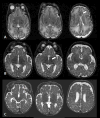

Figures